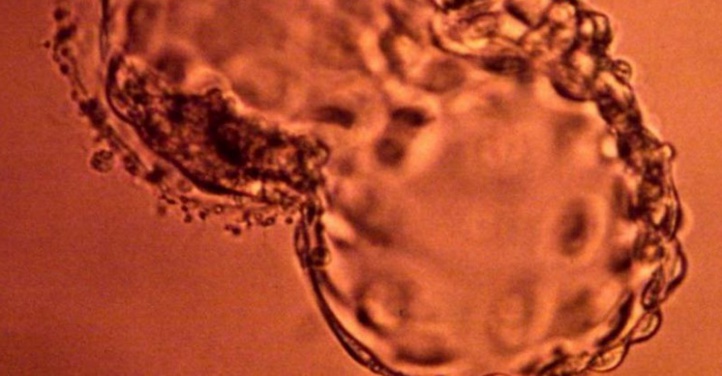

Une équipe de chercheurs chinois est parvenue à corriger une anomalie génétique sur des embryons humains porteurs d'une grave maladie héréditaire du sang, la thalassémie, une première prudemment saluée jeudi par d'autres experts en génétique.

En utilisant une nouvelle technique d'édition génétique, qui modifie chimiquement l'ADN, les chercheurs de l'université Sun Yat-sen de Canton sont parvenus à corriger l'une des variantes de cette mutation sur des embryons humains non viables. La technique utilisée est adaptée de la méthode CRISPR/Cas9 (ou "ciseaux moléculaires") mais en ajoutant l'utilisation d'une enzyme, qui a permis de transformer avec précision la "lettre" mutée dans l'ADN par la "lettre" correcte, détaille l'étude, publiée en ligne samedi dernier dans la revue spécialisée Protein and Cell.